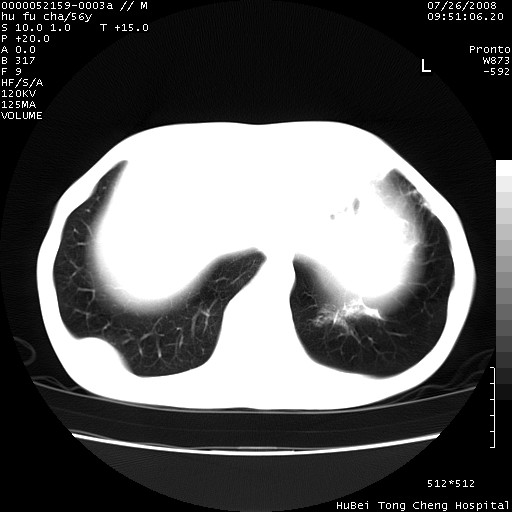

以下是引用zsl6918在2008-8-25 22:47:00的发言:[br]胸骨,胸椎及肋骨均可见多发转移表现,肝内低密度结节不除外转移。原发灶可能在右肺。双侧可见支扩表现。